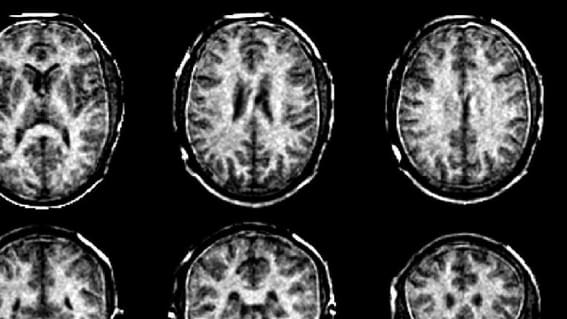

Visualisierung von MS  |  Bild: ETHZ

Das MRT-Verfahren der ETH schafft es, den Myelingehalt direkt zu messen – statt wie bislang indirekt über die Signale der Wasserstoffatome im Myelinwasser. Beim Konzept von Weiger, Baadsvik et al. werden MRT- Aufnahmen des Gehirns mit Zahlenwerten versehen, die zeigen, wie viel Myelin an einer bestimmten Stelle im Vergleich zu anderen Bereichen des Bildes vorhanden ist. Je dunkler der Bereich und je kleiner die Zahl im Bild, desto schwächer sind die Myelinscheiden.

Die MRT-Scans zeigen numerisch, wie viel Myelin an einer bestimmten Stelle im Vergleich zu anderen Bereichen des Bildes vorhanden ist.  |  Bild: ETH Zürich.